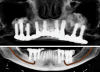

Fig 19. CBCT at 20-year follow-up.

Figure 19

In 2020, the patient presented to the NYUCD Periodontology and Implant Dentistry Clinic. A clinical examination and radiographic evaluation showed that the patient's maxillary arch still exhibited good peri-implant soft-tissue health and stable marginal bone level with slight bone loss on implants Nos. 2, 6, 8, and 11 (Figure 18 through Figure 20). The maxillary prosthesis showed adequate stability with a slight chipped suprastructure on the porcelain on the right side. The patient was advised to substitute the implant-supported, screw-retained hybrid acrylic complete denture in the maxilla with a fixed, implant-supported, screw-retained prosthesis, which she declined due to financial considerations.